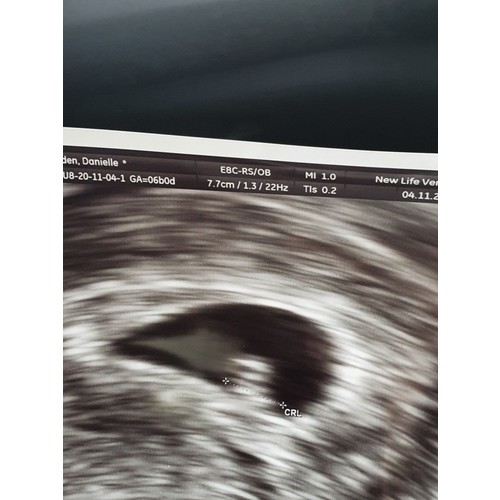

Dit was mijn echo 5+5 ( er staat geloof ik ander termijn op , ik was echt veel terug gezet, door een gemiste menstruatie die dus eigenlijk gewoon gemist was en geen zwangerschap was )

Ze twijfelden wel of het goed zat, want groeide eerst ook niet lekker, met 7 weken terug gegaan voor een echo en het was gewoon gegroeid en zit prima ! Onderhand 30+4 van ons mannetje !

Deze echo was ik 6w3d (ik dacht zelf verder te zijn). Ook bij mij dachten ze dat t niet goed was, omdat het te klein zou zijn. Ben op dit moment inmiddels 17w zwanger. Houd hoop en ik duim met je mee!